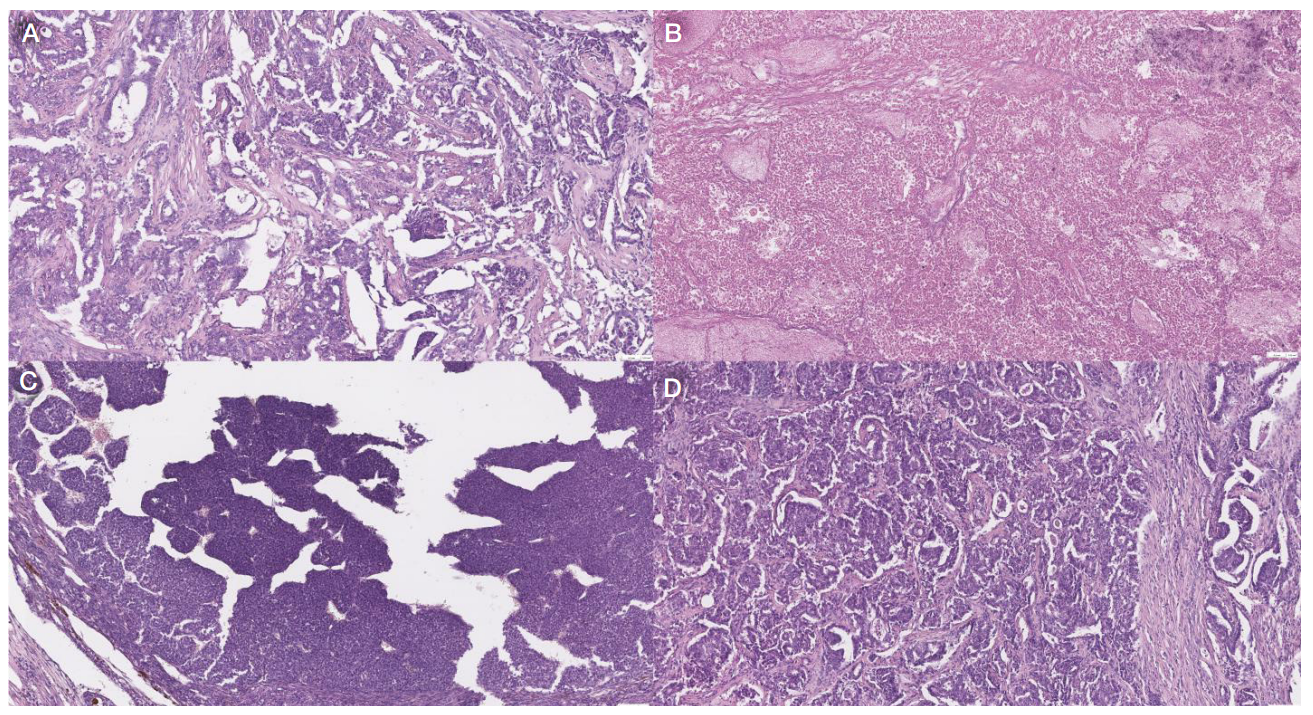

Fig. 2. Microphotographs of the sections of tumor specimens obtained from laboratory animals No. 7 (А), No. 8 (B), No. 9 (C), and No. 6 (D), 10× magnification. Hematoxylin and eosin stain